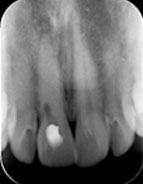

- Ống tủy bị caxi hóa khiến cho việc tìm ống tủy vô cùng khó khăn việc làm sạch, tạo hình tỉ mỉ và mất thời gian.

Ống tủy bị caxi hóa sẽ giảm xác suất thành công sau điều trị